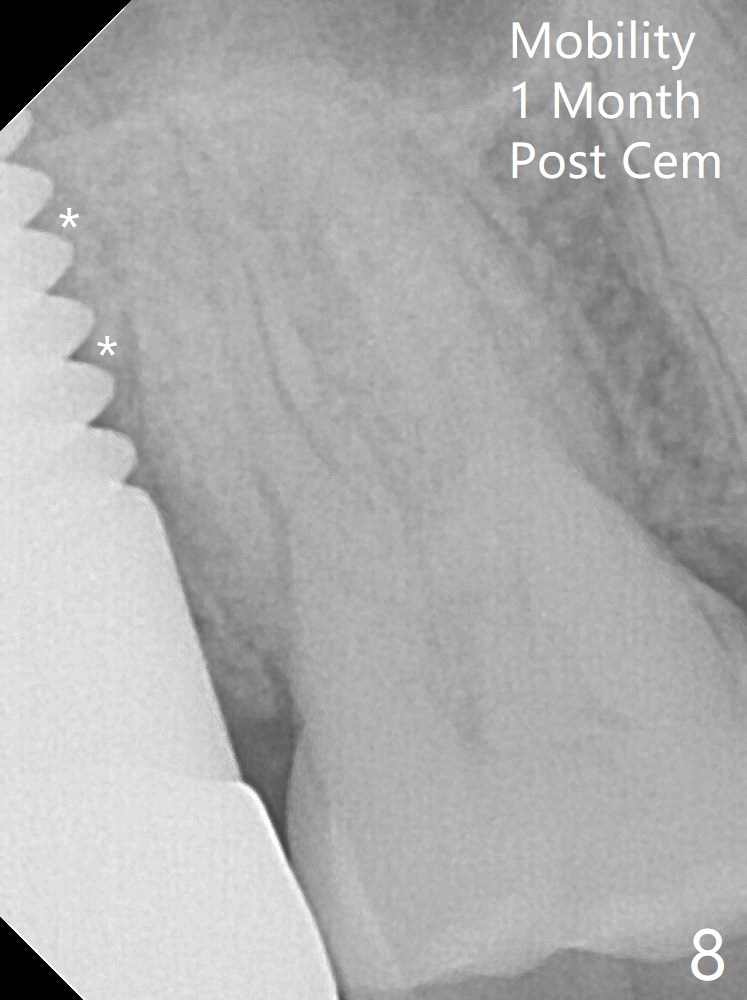

Preop exam shows that the tooth #2 has split into the buccal (Fig.1 B) and palatal (P) halves. When the tooth is extracted (Fig.2), there is a large piece of granulation tissue between these halves. The socket is large with sinus floor having pointed perforation. The latter is enlarged with rounded tapered Tatum osteotomy 2-4 mm, followed by tapered and then rounded taps. A 6.8x14 mm rounded tap has barely enough stability (Fig.3). Following placement of 2 PRF plug and 2 PRF membranes and allograft/Osteogen, a 8x17 mm cylindrical implant is placed with 60 Ncm (implant machine reading), however the implant is unstable (Fig.4). More graft is placed around the implant. With placement of 6x3 mm abutment, an immediate provisional is fabricated to close the socket. There is nasal discharge for a few days postop. PAs taken nearly 6 months postop show no bone loss (Fig.5,6). The definitive crown is cemented with access hole; there is no residual cement (Fig.7 (9 months postop)). The crown is loose 1 month post cementation (last March, Fig.8 with periimplant space (*)). The unipost was not cemented due to gag reflex. He refuses treatment immediately because of the allergy season. When he returns, spray a topical to his throat. Following crown removal, implant is found to have mobility. Panoramic X-ray (Fig.9) and CT (Fig.10,11) show fibrointegration (space) and implant intrusion into the sinus (S) without bone formation. After implant removal, the sinus floor and membrane are found to have been perforated. Osteogen plug is placed, followed by Vanilla/Osteogen (Fig.12 *) and Osteogen plug. It appears that an immediate implant is contraindicated when there is severe infection (Fig.2) with sinus floor perforation. In this case, the bone density at the upper 2nd molar is low (Fig.10 distopalatal view of 3-D image). Bone expansion and condensation is needed for implantation. Progressive loading is also necessity prior to impression.